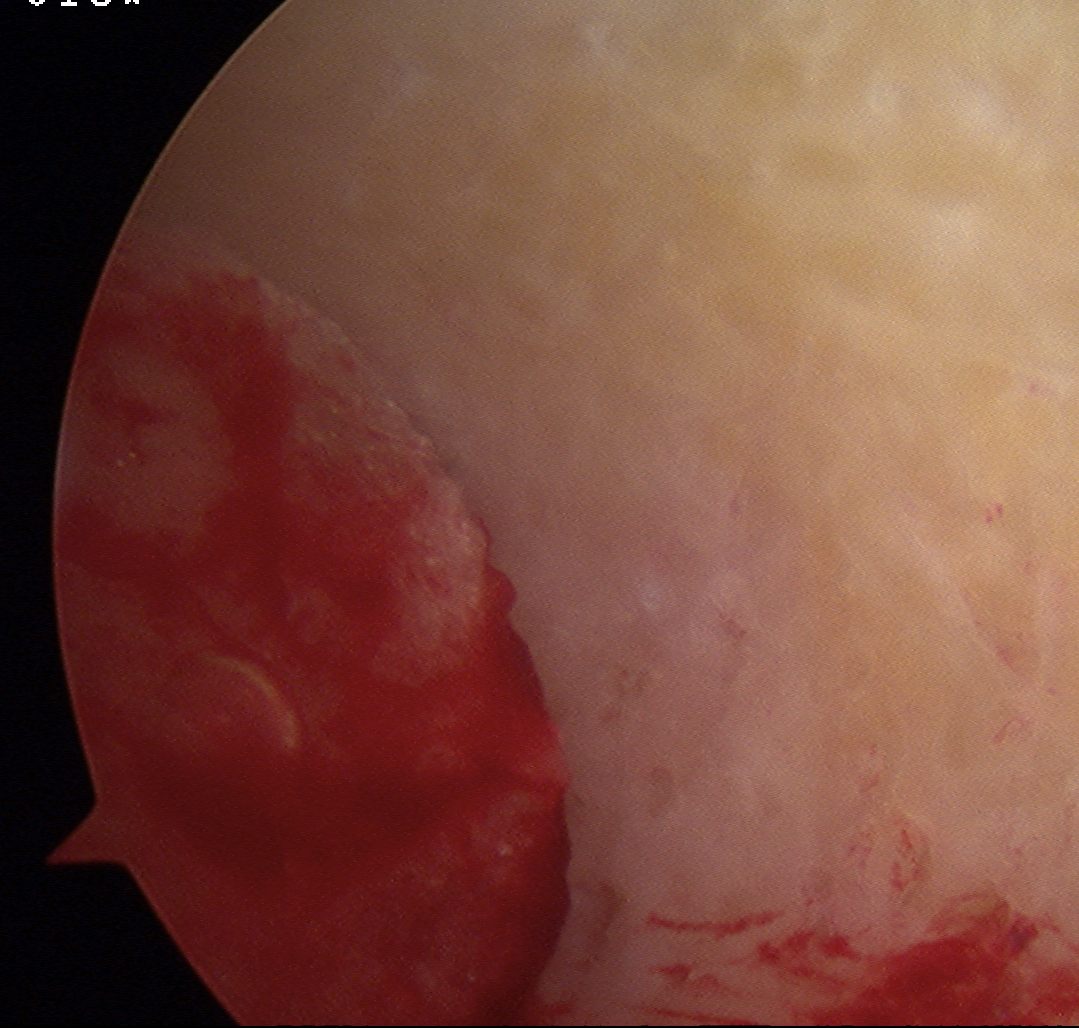

Failed ACL with tibial tunnel too posterior and with lysis

Tunnels debrided / redrilled and synthetic bone plugs inserted